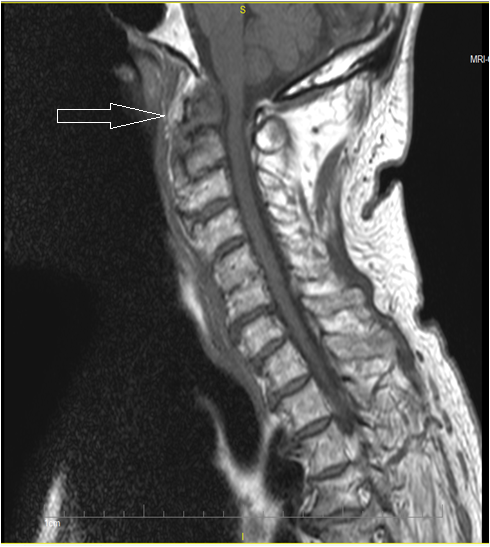

A 43-year-old woman had worsening thoracic and lumbar pain associated with tingling and tightness in the anterior upper and lower abdominal area. An urgent MRI of the thoracic spine showed a soft tissue mass that extended from C7 to T4 and involved the prevertebral, paravertebral, and intraspinal spaces (arrow); this caused compression and posterior displacement of the spinal cord and an anterior T2 vertebrae compression fracture.